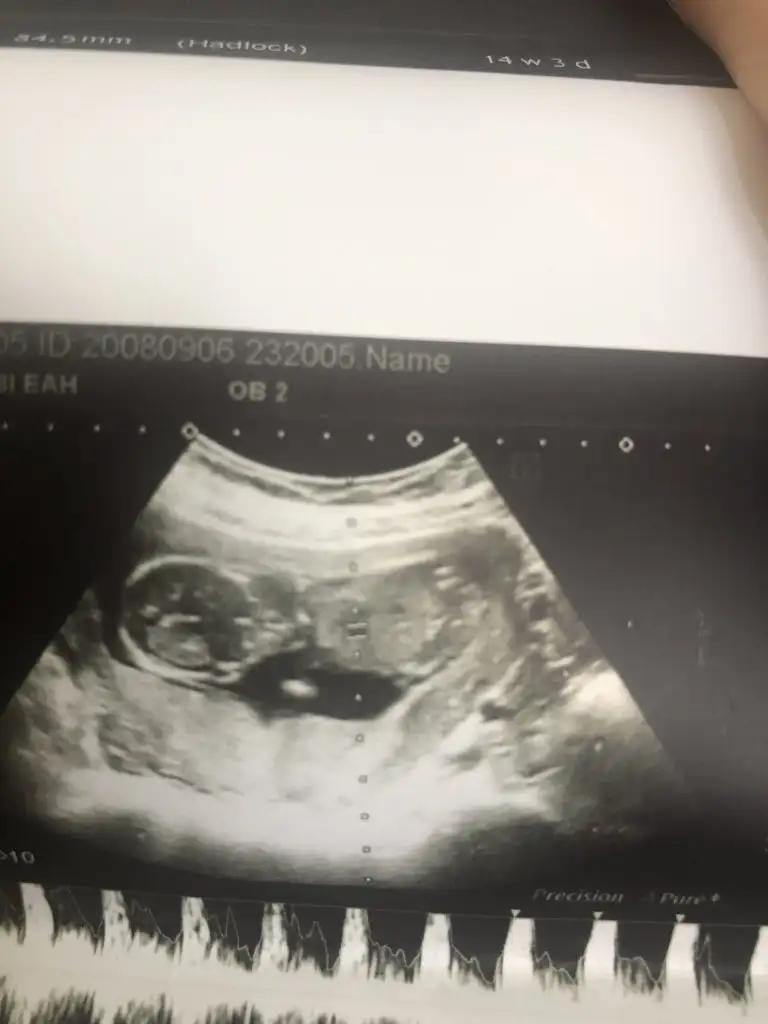

Bu bacak arası evet. Benim de ilk erkek olarak söylemişti doktorum sonra kız oldu. Hala tereddütteyim ben de. Detaylıya kadar bekliyoruz o yüzden :)Ya arkadaşlar bebeğim 16 haftalık bugün 4 lü tarama için gittim 16 hafta boyunca bebeğe erkek diyen doktor bugun de kıza benziyo dedi şaştım kaldım nasıl öğrencem ben cinsiyeti doğru hangisi ? EKLEDİĞİM GÖRSELDE BACAK ARASINI MI ÇEKTİ BİLMİYORUM BAKAR MISINIZ

16 haftaya kadar her gittiğimde erkek çıkıntısı var dediler 16. Haftada kız dedi doktorKız gibi canım bana öyle geldi çünkü erkek de çıkıntı hemen belli oluyor bunda hiç çıkıntı yok ve 16. Haftaya kadar çok çok daha belli olurdu

16 haftaya kadar bacak arasını görerek mi çıkıntı var dedi? Yoksa yandan mı bakıyordu? Birde 16.haftada bacak arasına baktığında üç çizgiden bahsetti mi?16 haftaya kadar her gittiğimde erkek çıkıntısı var dediler 16. Haftada kız dedi doktor

Bebeği 16. Haftaya kadar böyle görerek söyledi dünde dörtlü taramada tek tek vücudunu ölçerken kız dedi ama erkek demiştiniz dedim bak çıkıntısı yok kıza benziyo yani dedi şaşırdı o da erkek mi demişim dedi16 haftaya kadar bacak arasını görerek mi çıkıntı var dedi? Yoksa yandan mı bakıyordu? Birde 16.haftada bacak arasına baktığında üç çizgiden bahsetti mi?

Üç çizgi falan hiç bahsetmedi sadece bacak arası boş dedi16 haftaya kadar bacak arasını görerek mi çıkıntı var dedi? Yoksa yandan mı bakıyordu? Birde 16.haftada bacak arasına baktığında üç çizgiden bahsetti mi?

Ama bacak arasını net görmemiş demekki… keşke net görmüyorsa söylemeseler… yani benim 12 haftada bacak arası boştu ama yandan bakınca vardı çıkıntı… kızda da da erkekte de bu haftalarda olur çıkıntı oyüzden bacak arasını görmek lazım… instagramda mehmet boz’un videolarını bak cinsiyetle ilgili… aslında çok net oluyor her şey…Bebeği 16. Haftaya kadar böyle görerek söyledi dünde dörtlü taramada tek tek vücudunu ölçerken kız dedi ama erkek demiştiniz dedim bak çıkıntısı yok kıza benziyo yani dedi şaşırdı o da erkek mi demişim dedi